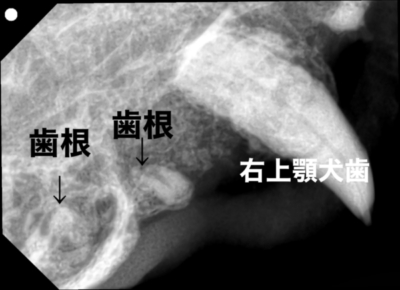

すると、その先端は先ほど膿が出ていた犬歯の後ろではなく、前臼歯のあった場所に出てきました。見た目では歯はありませんでしたが、歯科レントゲンではいくつかの残根が認められました。

レントゲンで確認できる歯根を歯肉を切開し数箇所摘出し、重度の歯周炎の下顎犬歯、口腔鼻腔ろうとなっている上顎剣犬歯も抜歯し、手術は修了しました。